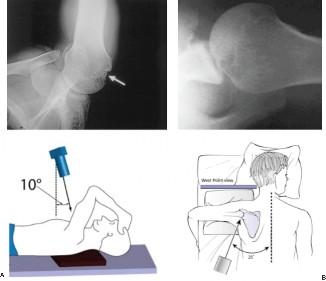

The correct answer is (C). Each RC tendon has specific tests for pathology. The supraspinatus strength test (aka Jobe test) is performed by abducting the shoulder to

90 degrees, bringing the arm in the scapular plane (30 degrees forward), and maximally internally rotating the arm (thumb pointing to the floor) (Fig. 2–1). The test is positive if weakness is found or if pain is experienced. Another test for the supraspinatus is the drop arm test. In the drop arm test, the arm is passively elevated by the examiner to the Jobe position, the patient is asked to attempt to keep it there, and the arm is released by the examiner. The test is positive if the patient is not able to keep the arm elevated and the arm drops.

Figure 2–1 Jobe test.

The belly press test (Answer A) and lift off test (Answer D) are used to evaluate for subscapularis pathology (Figs. 2–3 and 2–4). The hornblower test (Answer B) assesses the teres minor (Fig. 2–2). The external rotation lag test (Answer E) evaluates the infraspinatus.